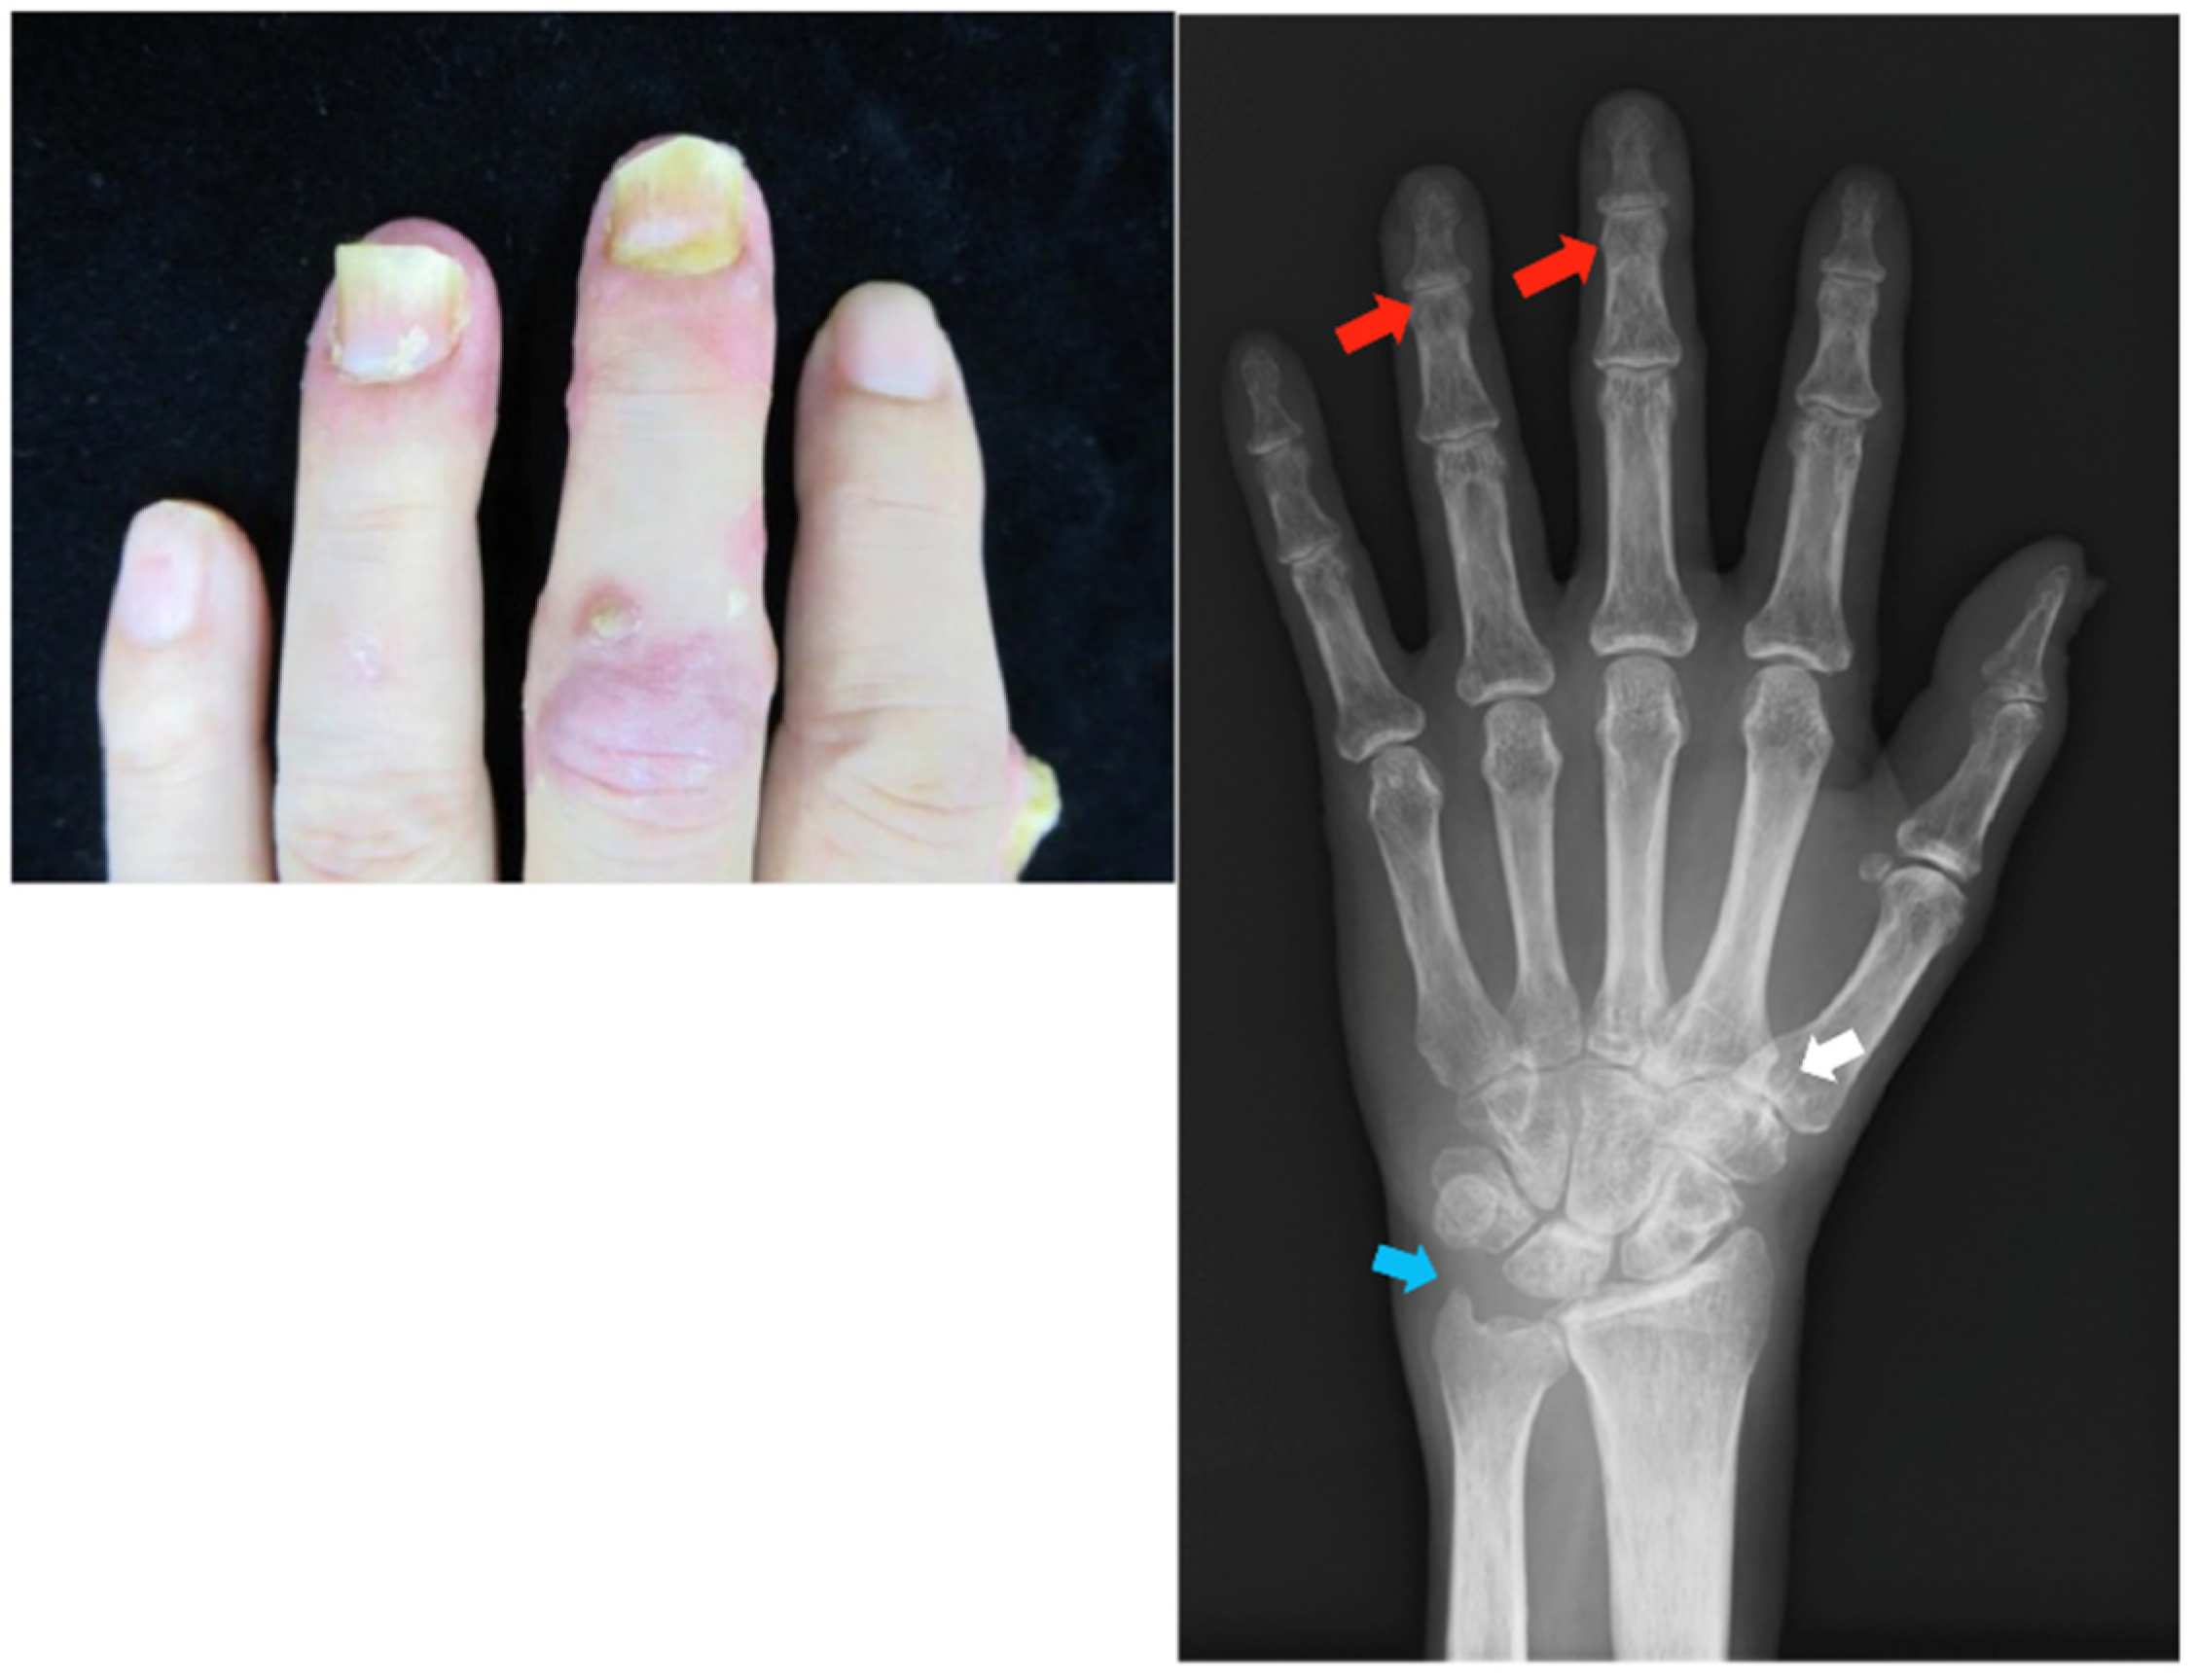

Clinical findings: There was erythema with white scales on the scalp, dorsum of the hands, and lower extremities (PASI score: 5.2). Onycholysis was observed in the left third and fourth fingers, and tenderness was observed in the same DIP joints. Crumbling was observed in the bilateral thumbs. Radiographs showed joint space narrowing, and the left styloid process was smaller than the right (Figure 2).

Figure 2.

Clinical photograph and radiograph of the hands in case 2. There is nail psoriasis in the left third and fourth fingers and tenderness in the same DIP joints. Joint space narrowing is depicted in the same DIP joints (red arrow). Additionally, joint space narrowing is shown in the left carpal joint (white arrow), and the left styloid process is smaller than the right one (blue arrow). DIP, distal interphalangeal.

Clinical findings: The patient had swelling and pain at the DIP joints of his hands and erythema with fine white scales on the scalp and low limbs (PASI score: 3.6). Pitting and onycholysis were observed on his hand nails. Bone proliferation was observed in the left third and fourth DIP joints due to PsA, marginal erosion in the left fifth proximal metacarpal and right thumb MCP, and narrowing of the joint space in the left carpal bone (Figure 4).

Figure 4.

Clinical photographs and radiographs of the hands in case 4. Swelling, pain, and redness are noted in the left second and right fifth joints. There is bone proliferation at the left third DIP and right first MCP joints due to PsA (red circle), marginal erosion in the left fifth proximal metacarpal and fourth PIP joints (red arrow), and joint space narrowing in the left carpal bone (blue circle). MCP, metacarpophalangeal; PIP, peripheral interphalangeal; DIP, distal interphalangeal.